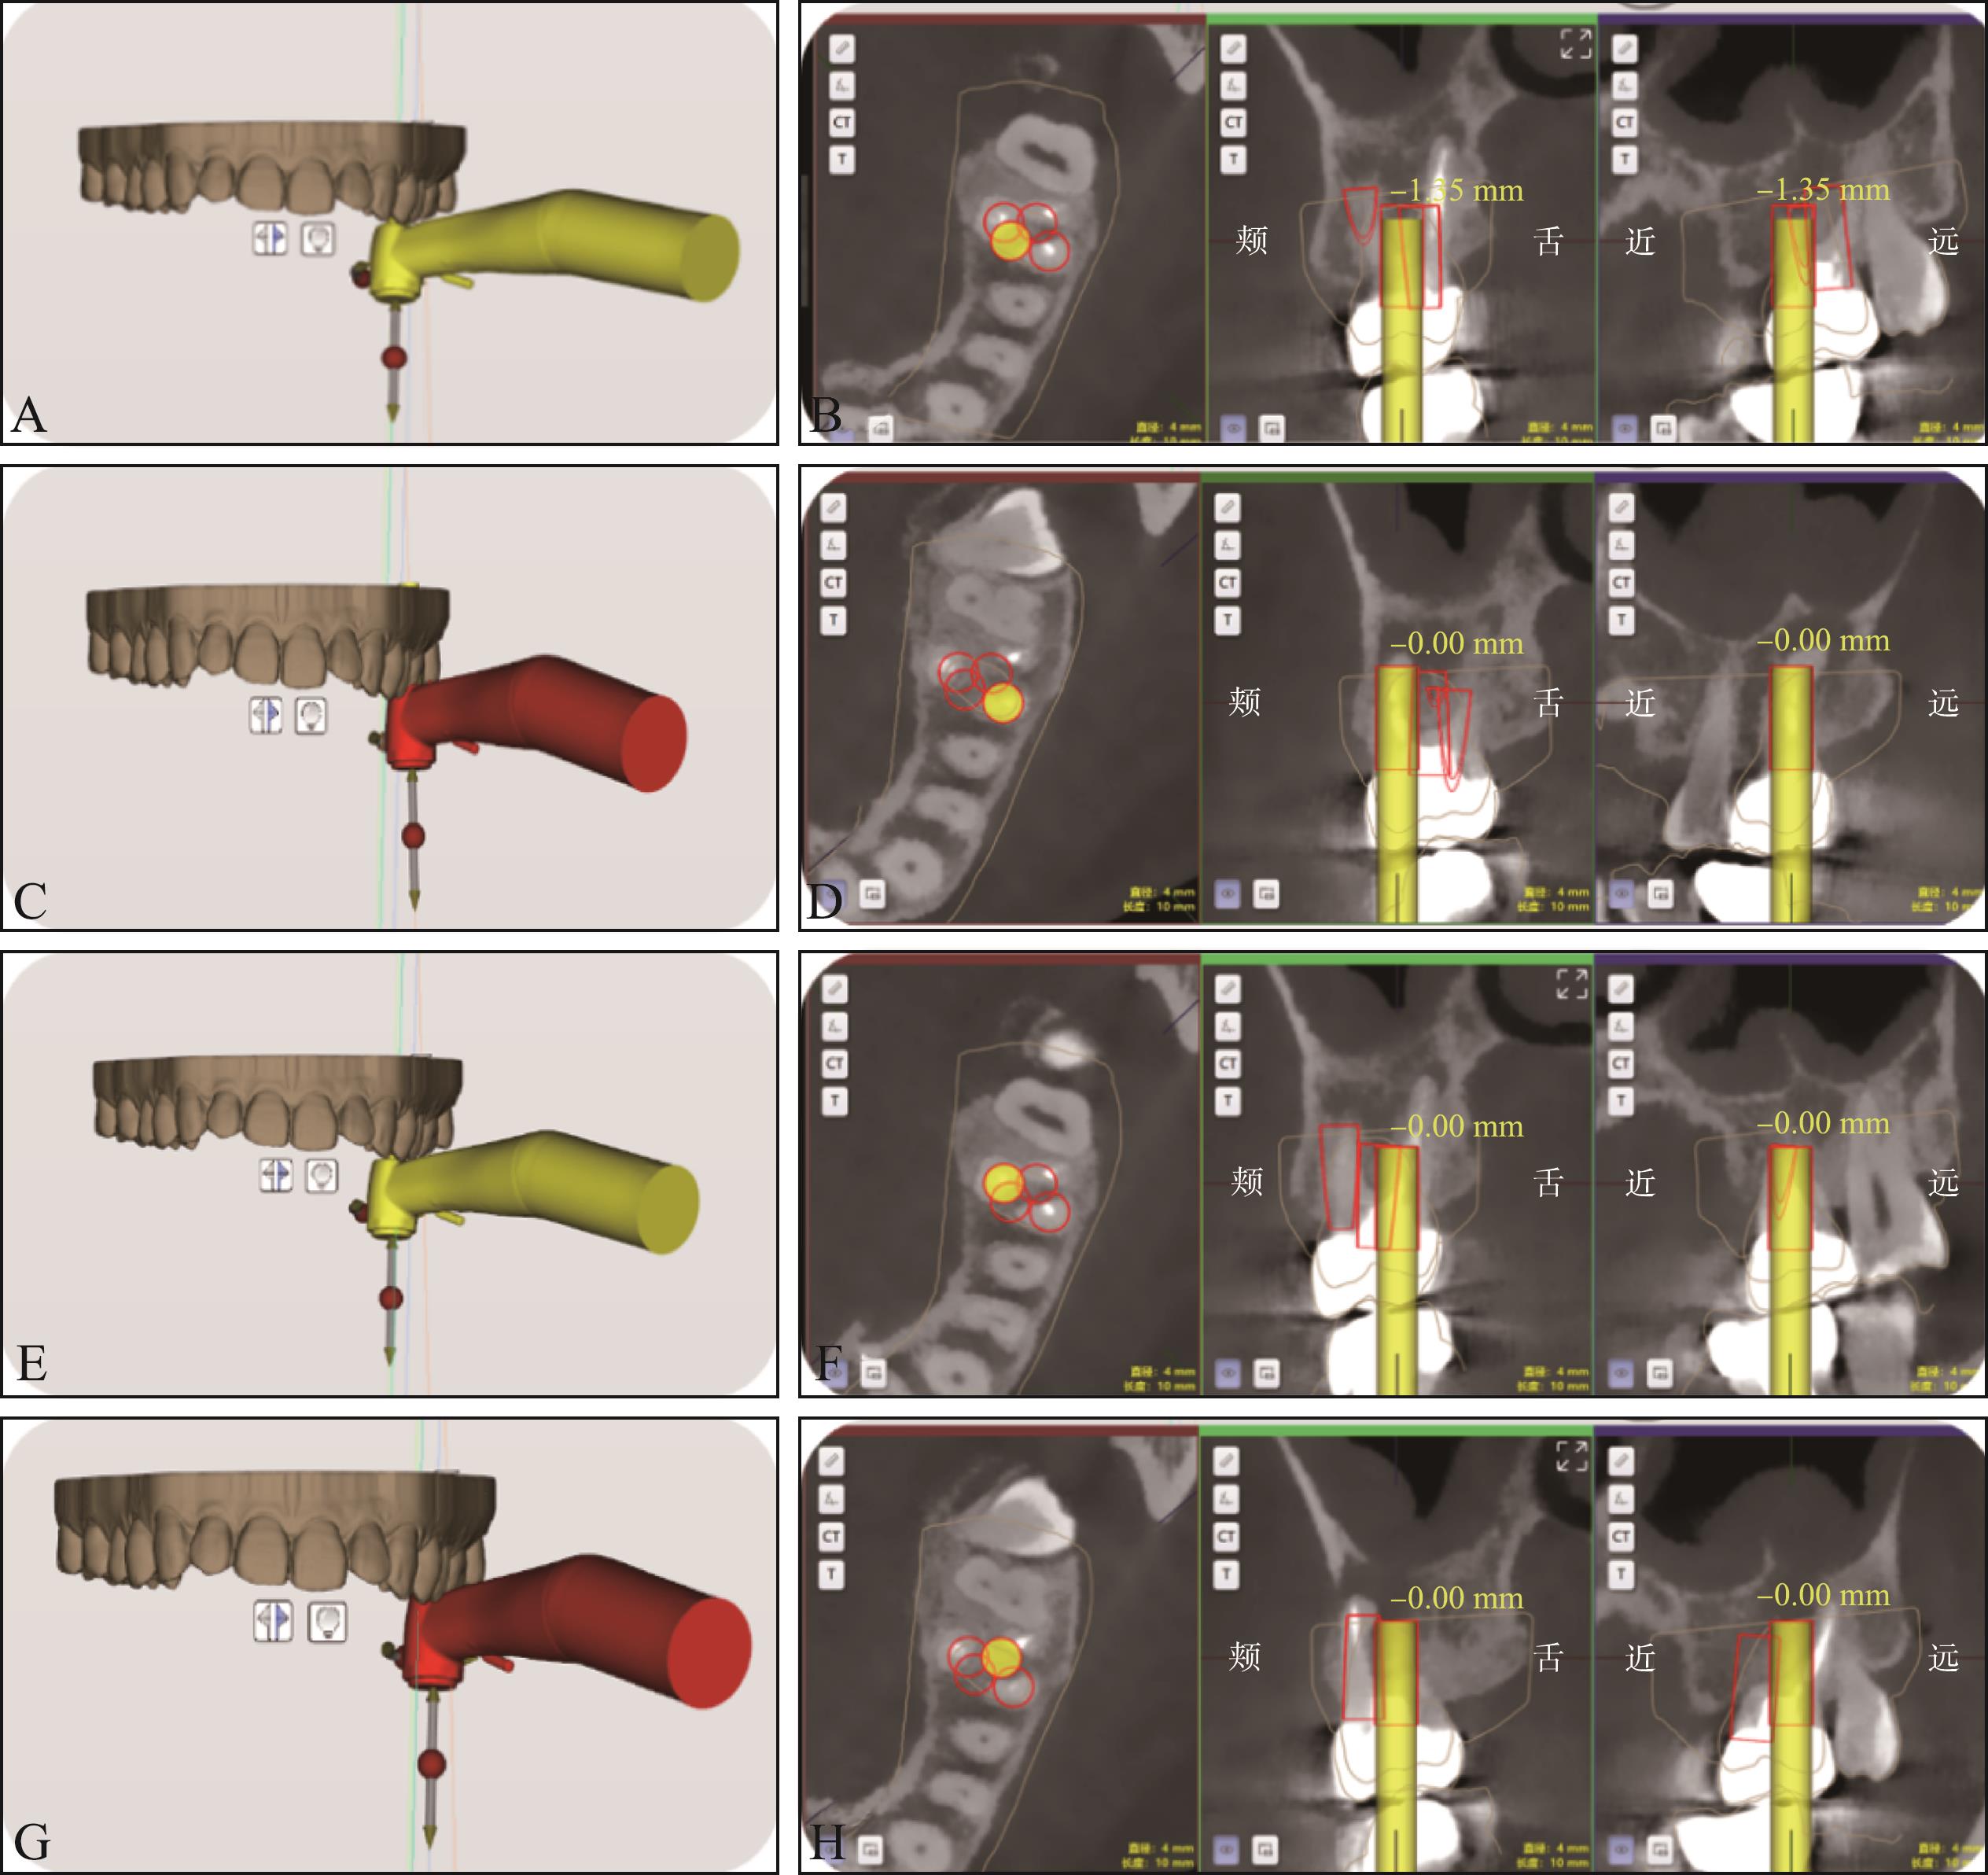

Zhang H, Cai M, Liu Z, et al. Combined application of virtual simulation technology and 3-dimensional-printed computer-aided rapid prototyping in autotransplantation of a mature third molar[J]. Medicina (Kaunas), 2022, 58(7): 953.

|

Liu C, Li Y, Wang F, et al. Development and validation of a robotic system for milling individualized jawbone cavities in oral and maxillofacial surgery[J]. J Dent, 2024, 150: 105380.

Riad Deglow E, Lazo Torres NZ, Gutiérrez Muñoz D, et al. Influence of Static navigation technique on the accuracy of autotransplanted teeth in surgically created sockets[J]. J Clin Med, 2022, 11(4): 1012.